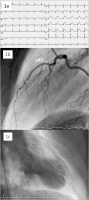

Abbildung 2a-c: a): ECG one day after the first coronary angiography showing subacute anterior STEMI; (b): ECG three days after the first coronary angiography showing again significant anterior ST segment elevations; the patient once again developed massive retrosternal chest pain; (c): Second coronary angiography revealed complete occlusion of the proximal LAD due to spontaneous dissection.